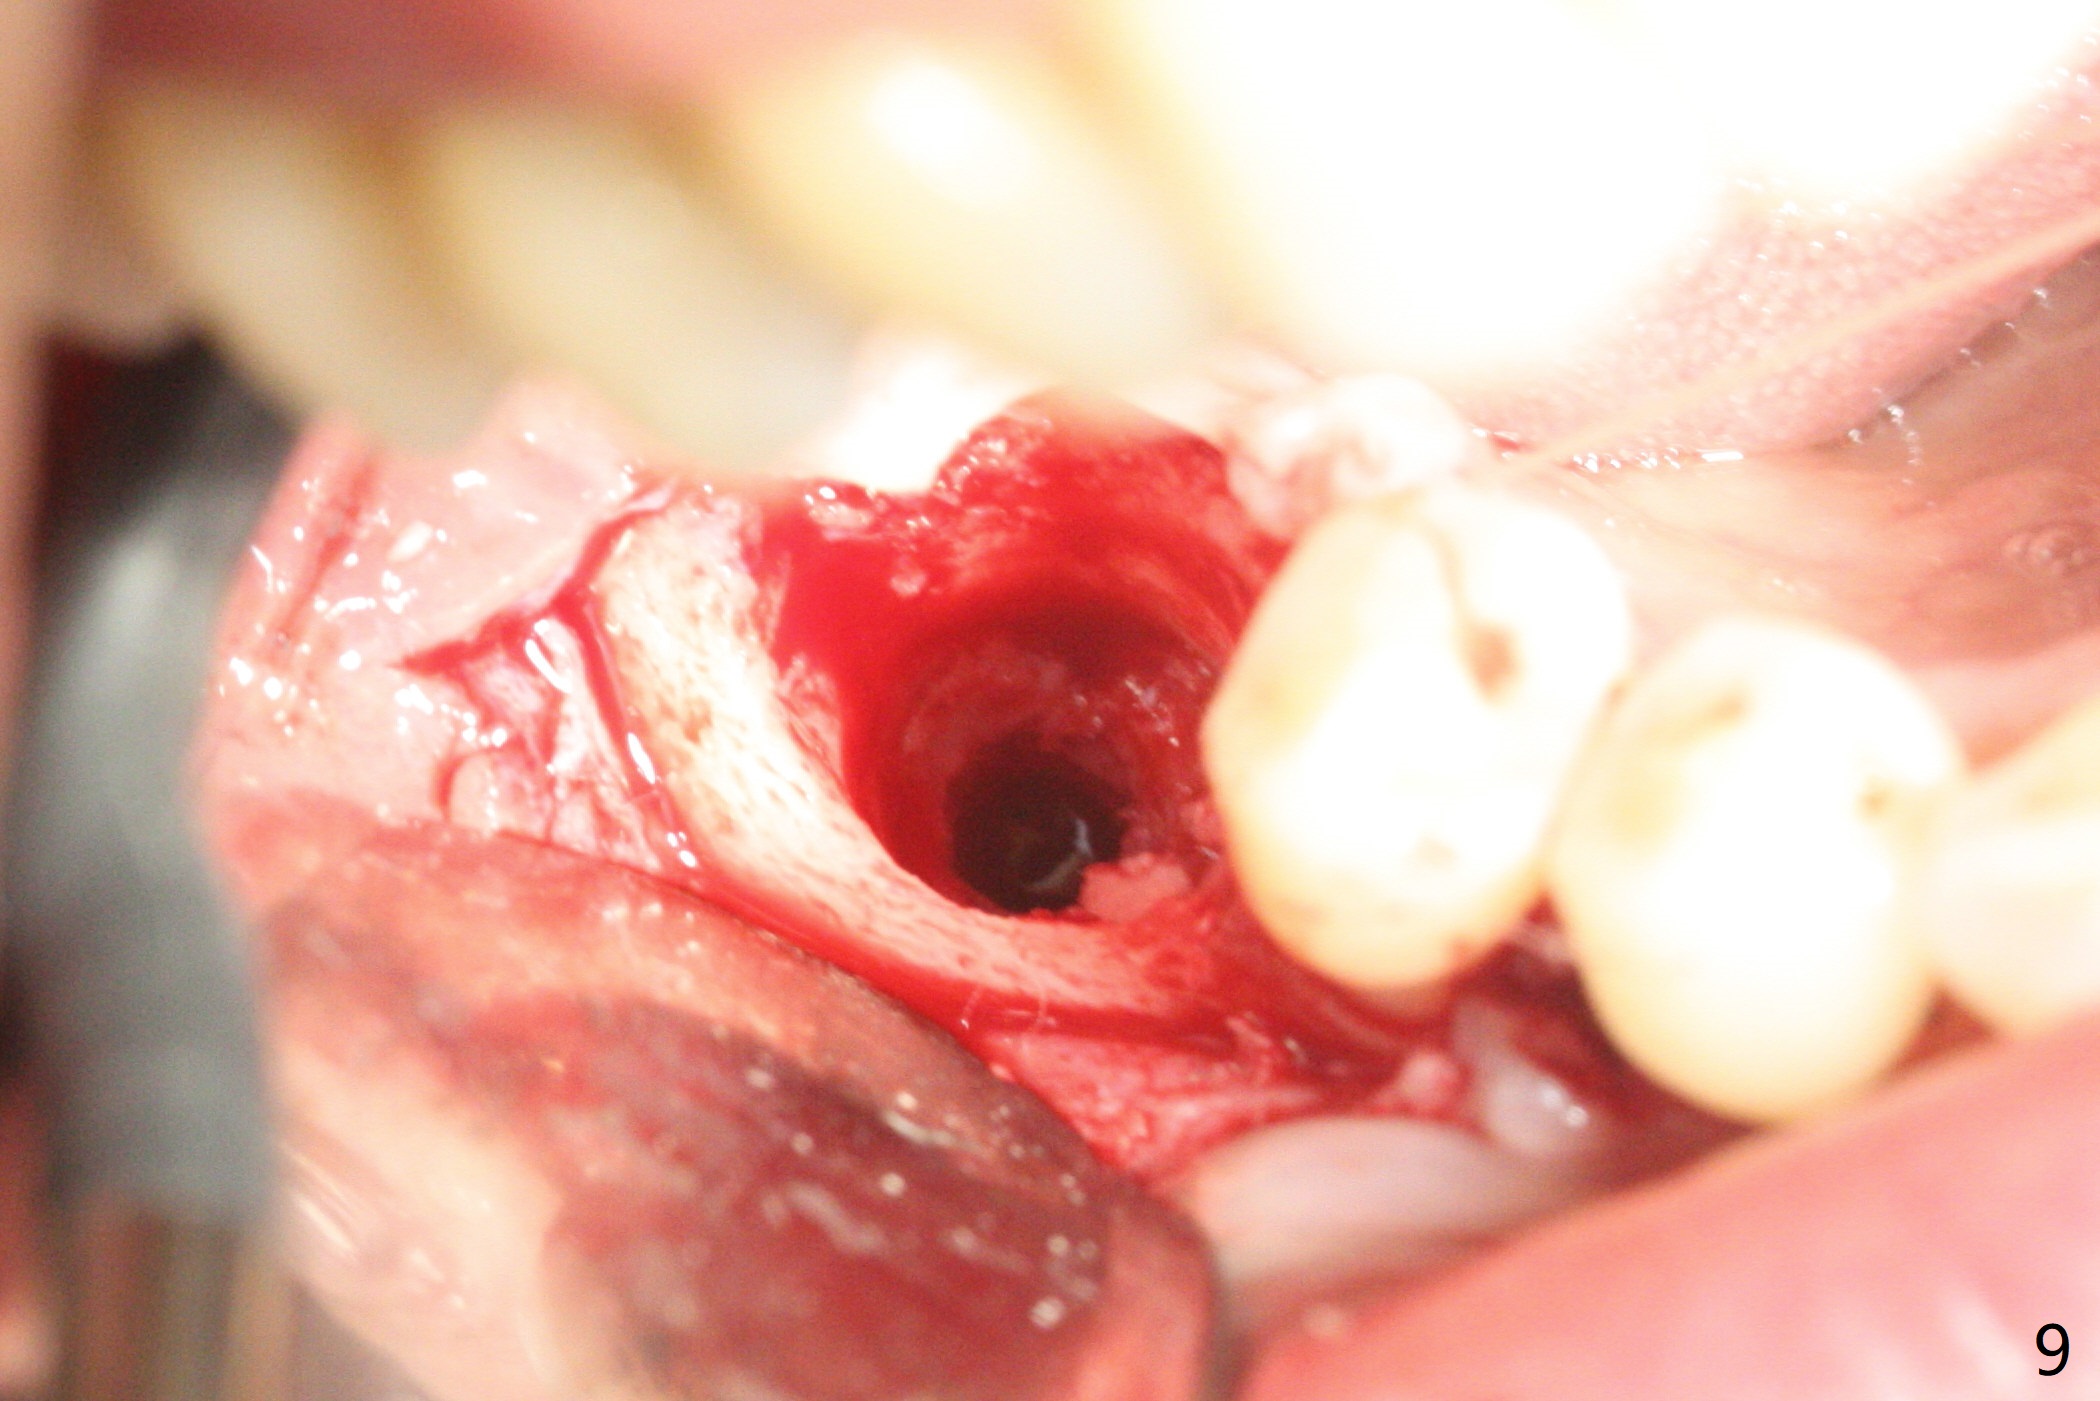

There are signs of periimplantitis at #30 eleven months postop (Fig.1 (* bone loss)). The bony defect (Fig.2) will be filled with allograft mixed PRF liquid to form sticky bone (Fig.3,4), followed by PRF membrane (not shown) and a piece of 6-month membrane (Fig.5). A hole is cut so that the 6-month membrane can slide down the abutment (Fig.2,5 A) to cover the bone graft around the implant (Fig.2,7 I). Setting acrylic is applied around the abutment and neighboring teeth for further protection and holding (Fig.8). The periimplantitis does not resolve nearly 7 months post graft. The implant will be removed. Prepare UF extra wide kit and try to insert 6.5 or 7.0 mm tap. Also prepare sticky bone and Cytoplast for wound closure. Implant removal involves surgical handpiece, 6.2/7 mm trephine bur, elevators, and implant driver. The defect is large (Fig.9) with the low buccal crest (Fig.10) and bone graft with PRF ("sticky bone") is placed, covered by PRF and 6-months membrane (Fig.11). The next implant will be placed with guide. If oral hygiene is not ideal, choose a bone level implant. The middle of the wound dehiscences slightly 8 days postop (Fig.12), accounting for mild loss of bone graft 1 year postop (Fig.14). The keratinized gingiva is apparently wide 1 year postop (Fig.13). There is mild loss of bone graft in the middle of the superficial area (Fig.14). The buccal plate seems to regenerate 1 year postop (pandemic delay, Fig.15).